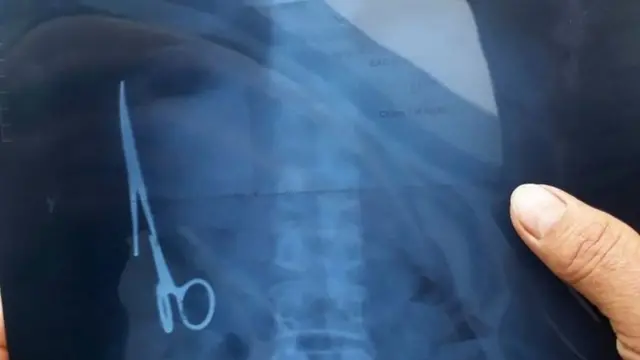

چند سال پیش پزشکان در ویتنام با بیماری مواجه شدند که درد شکم داشت و بعد از عکسبرداری با اشعه ایکس متوجه شدند قیچیای در شکم او است که ظاهرا از عمل جراحی ۱۸ سال قبل آنجا جا مانده است.

اینجا بیشتر بخوانید: قیچی جراحی هجده سال در شکم بیمار جا مانده بود